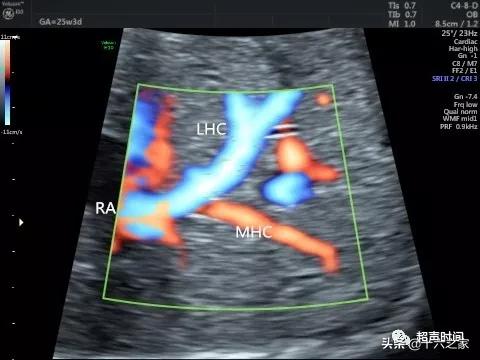

图 8 胎儿肝左和肝中静脉共干 , 共同进入右心房 。 LHC :肝左静脉;MHC :肝中静脉